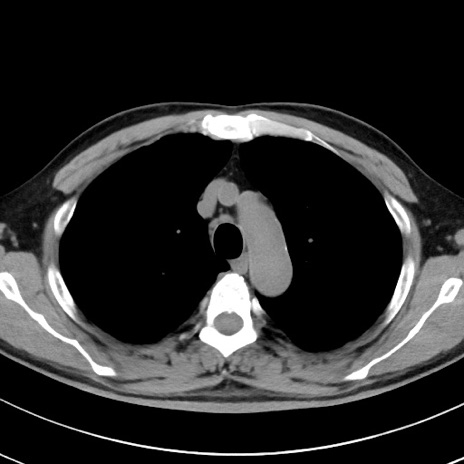

【腹部TIPS】症例29 参考症例 CT(横断像)

症例

70歳代男性